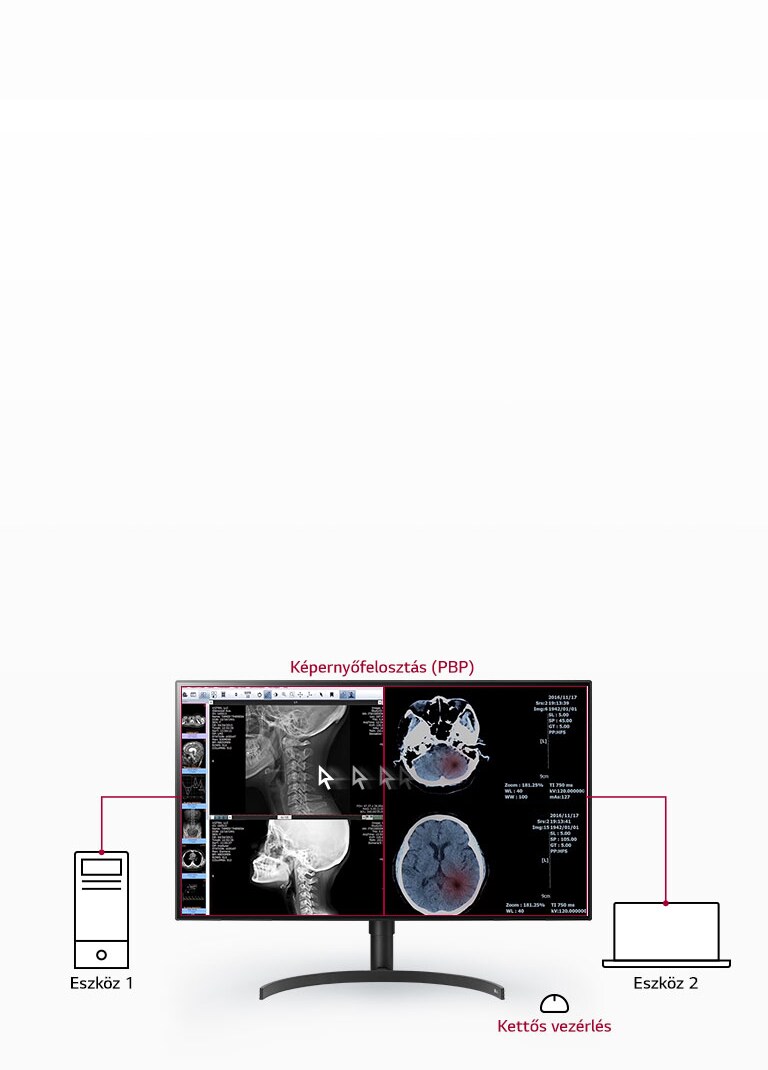

- PBP képernyőfelosztás és kettős vezérlés

A széles, 178°-os betekintési szög lehetővé teszi, hogy több szakember is azonos minőségben lássa a képeket. A monitor többfelbontású üzemmódot, PBP képernyőfelosztást és kettős vezérlést kínál, így több forrás egyszerre is megjeleníthető, növelve a munkafolyamat hatékonyságát.

PBP és kettős vezérlés – több jel, egy képernyőn

A képernyőfelosztás (PBP) és a kettős vezérlés lehetővé teszi, hogy egyszerre több, a monitorhoz csatlakoztatott eszközt irányítson egyetlen billentyűzettel vagy egérrel. Így az információk áttekintése egyszerűbbé válik, és több adatot láthat egyidejűleg, egyetlen képernyőn.

Hatékony munkafolyamat: PBP és többfelbontású mód egyszerre több jel megjelenítésére